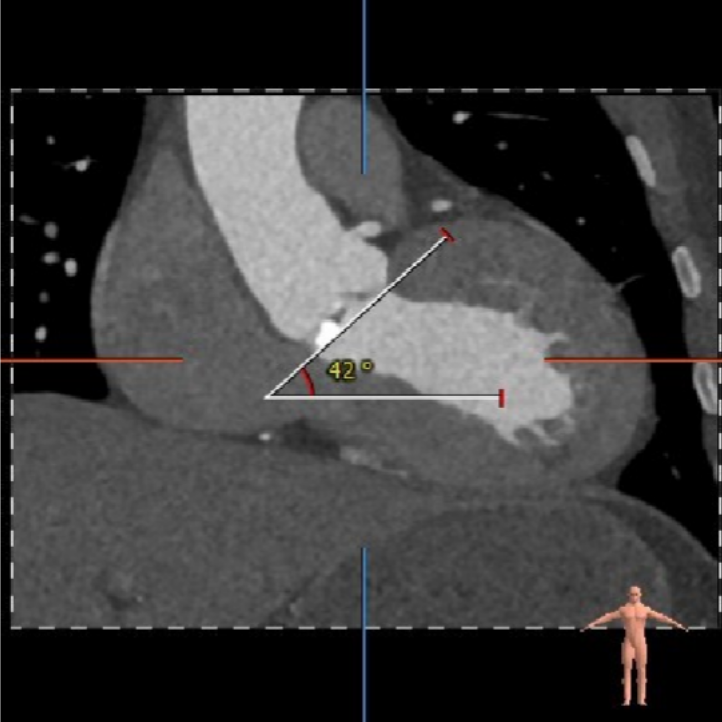

CT数据显示该患者为Type1主动脉瓣。

主动脉瓣瓣环周长80.8mm,平均周长径 25.7mm,SOV:34.8mm*34.3mm*33.4mm,瓣叶增厚,瓣上见右无钙化嵴,瓣环水平夹角42°。

冠脉高度测量

左冠开口高度15.5mm

右冠开口高度20.0mm